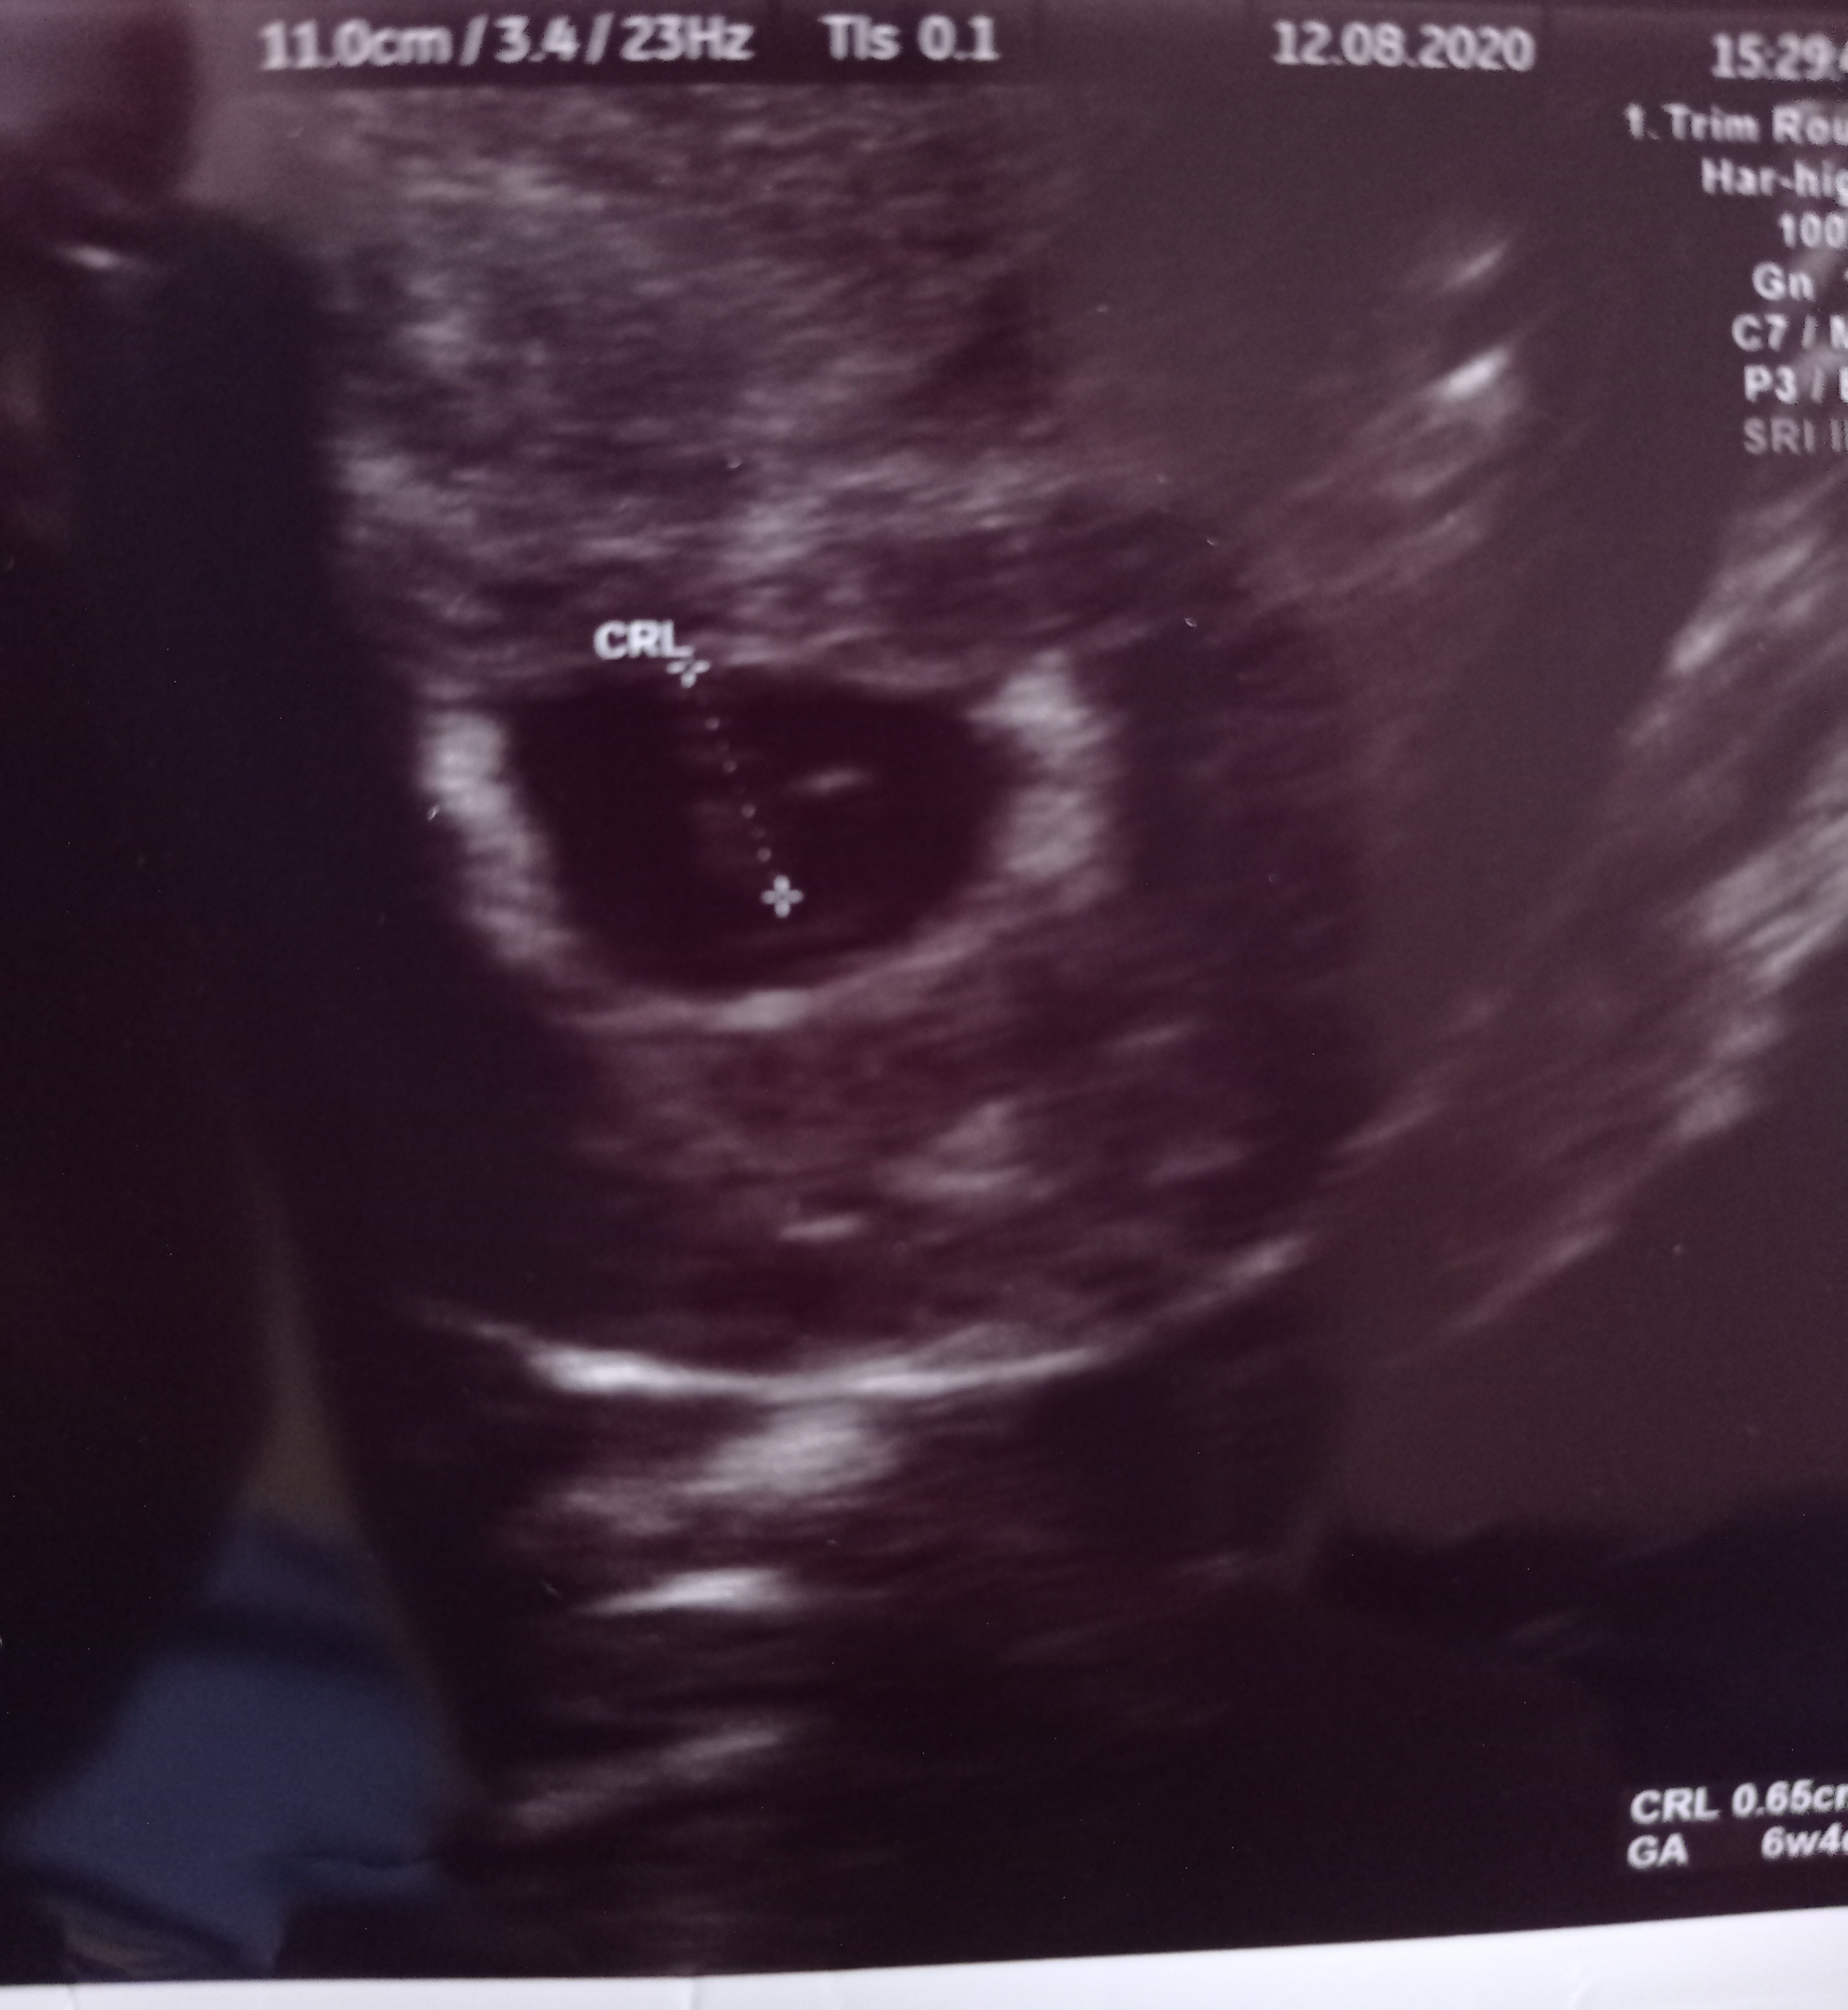

Teraz jest Ci źle i to w pełni zrozumiałe. I pewnie nie widzisz większych nadziei. Ale naprawdę pomyśl, że masz 50% szans na dziecko. Postaraj się odpoczywać bo stres nie jest dobrym doradcą. Ściskam cię mocno bo dokładnie to samo przeżywałam dwa tygodnie temu. To mój pęcherzyk z wtedy, zauważ że jest "bardziej" pusty.